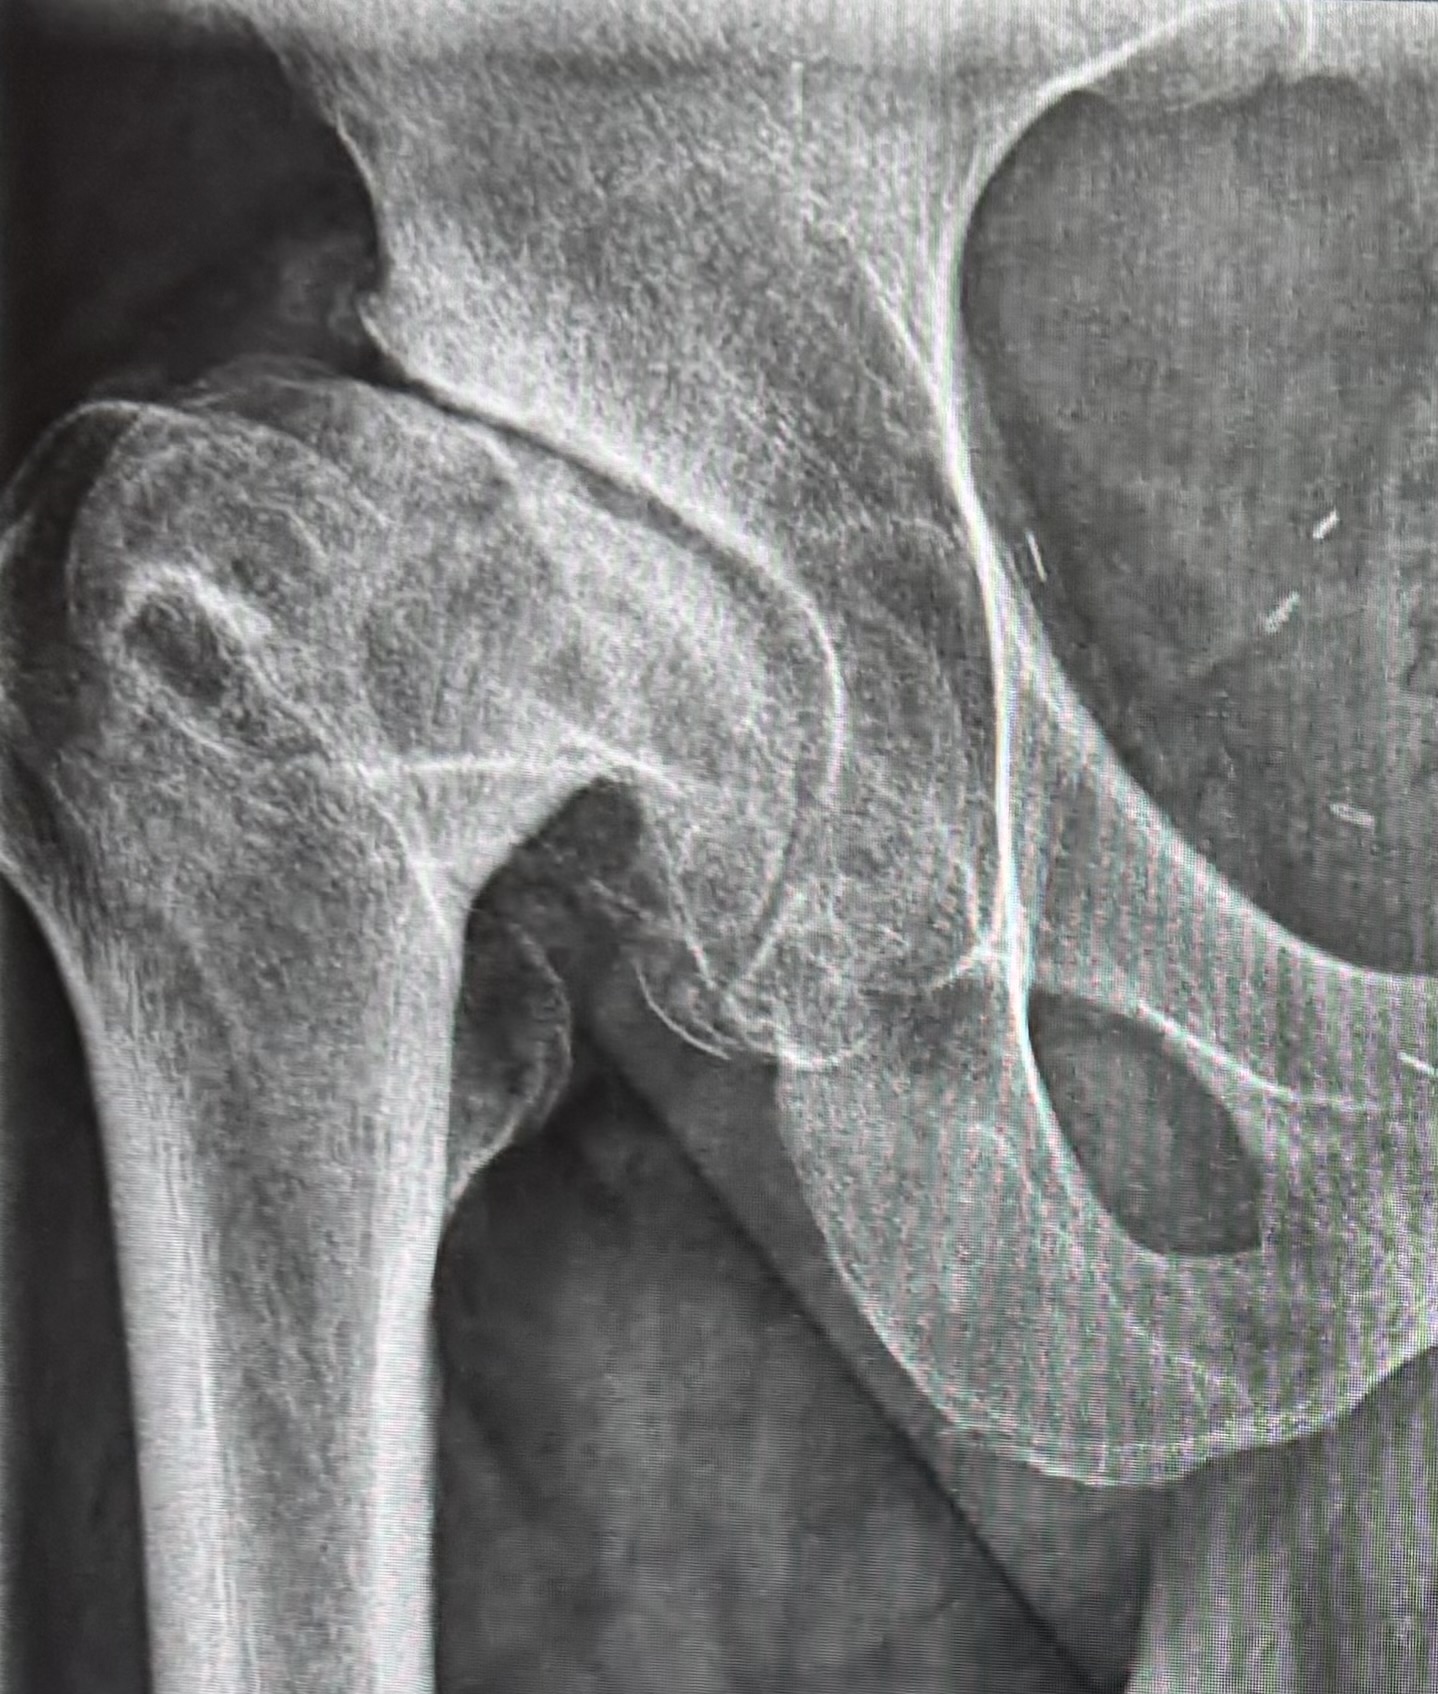

Schon vor dem Kindergartenalter wurde bei mir Morbus Perthes diagnostiziert. Das bedeutete, dass mein Hüftkopf nicht richtig durchblutet wurde und abstarb. Das Ergebnis war eine völlig deformierte Hüfte, mit der ich aufgewachsen bin. Wenn mir damals jemand gesagt hätte, dass ich mit diesem Gelenk bis zu meinem 51. Lebensjahr durchhalten würde, hätten die meisten Ärzte wahrscheinlich ungläubig den Kopf geschüttelt.

Der Bericht liest sich wie ein handwerklicher Krimi. Die Diagnose lautete: Fortgeschrittene sekundäre Koxarthrose bei Dysplasie und Z. n. Perthes. Auf Deutsch: Mein Gelenk war nicht nur verschlissen, es war durch die Kinderkrankheit auch völlig falsch geformt.

Was die Operateure vorgefunden haben:

- Massive Verformungen: Der Hüftkopf war „komplett entrundet und abgeplattet“, dazu riesige „Osteophyten“ (Knochenwucherungen), die sich über die Jahre gebildet hatten.